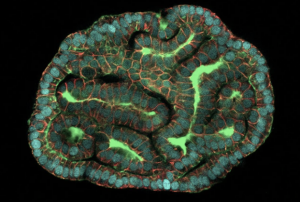

Araştırmacılar ilk kez doğrudan devam eden gebeliklerden alınan hücrelerden organoidler (dokuyu taklit eden 3 boyutlu hücre demetleri) yetiştirdi. Hücreler, çalışmadan bağımsız olarak standart prosedürler sırasında 16. ve 34. gebelik haftaları arasında büyüyen fetüslerin etrafındaki amniyotik sıvıdan çıkarıldı. Ekip, üç organdan (ince bağırsaklar, böbrekler ve akciğerler) organoidler üretti ve aynı zamanda bu bozukluktan etkilenen örneklerden alınan hücreleri kullanarak, diyaframın doğru şekilde gelişemediği bir hastalık olan konjenital diyafram hernisini modelledi. Pluripotent kök hücrelerden yapılan organoidlerin aksine, amniyotik sıvı hücreleri zaten bir organ kimliğine sahiptir. Kök hücre biyoloğu ve çalışmanın ortak yazarı Mattia Gerli, “Yeniden programlama yok, manipülasyon yok” diyor ve “hücrelerin potansiyellerini ifade etmelerine izin veriyoruz.”